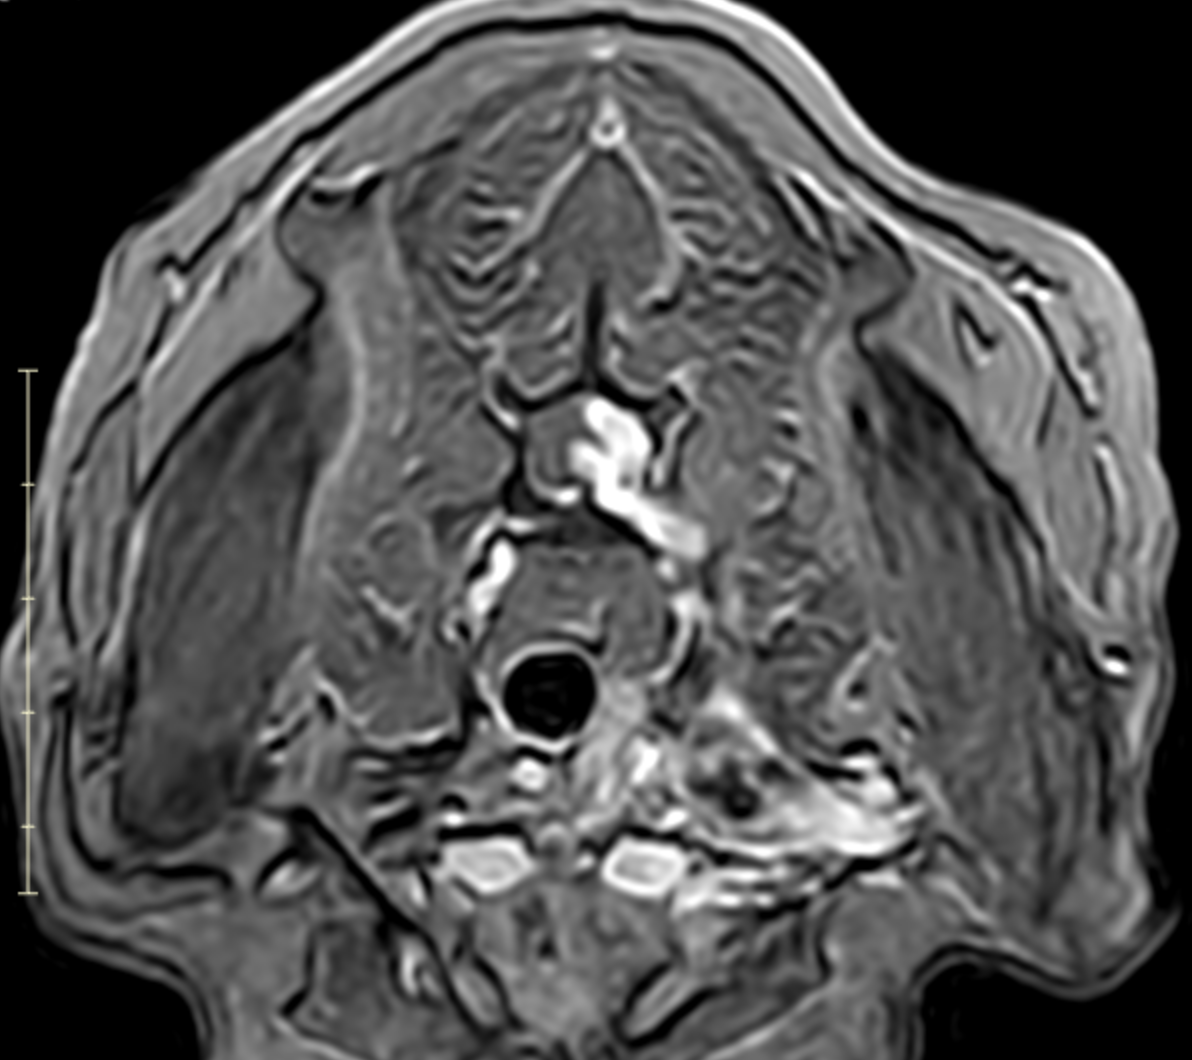

Transverse MRI of a dog showing enlarged C7 to T1 nerve roots with contrast enhancement and spinal cord displacement

Image 7. Transverse post-contrast MRI showing asymmetric enlargement and contrast enhancement of the left C7–T1 nerve roots with associated spinal cord displacement, consistent with a nerve sheath tumor.

MRI revealed a clinically significant and previously undetected diagnosis (Images 5-7):

Primary Diagnosis: Nerve Sheath Tumor

• Contrast-enhancing mass involving the left C7, C8, and T1 nerve roots

• Extension from the spinal canal through the intervertebral foramen into the axilla and brachial plexus

• Severe spinal cord compression with displacement

• Expansion of the C7–T1 neural foramen

• Associated neurogenic muscle atrophy of the left forelimb (triceps)